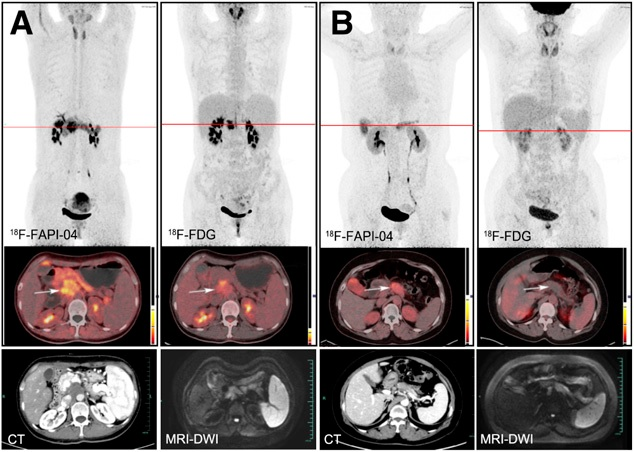

A group led by Dr. Nader Hirmas of the University of Duisburg-Essen in North Rhine-Westphalia, Germany, analyzed preliminary data from a prospective phase II study of Ga-68 FAPI-PET compared with F-18 FDG-PET in patients with sarcoma, pancreatic carcinoma, and primary brain tumors. According to the findings, Ga-68 FAPI-PET may be considered a new tool for tumor staging, the authors wrote.

"Ga-68 FAPI demonstrates higher absolute uptake in pancreatic cancers and sarcoma, as well as higher tumor-to-background uptake along with improved tumor detection for pancreatic cancers, sarcoma, and other tumor entities," they explained.

The investigators found that Ga-68 FAPI outperformed F-18 FDG across a variety of measures for pancreatic cancers and sarcomas.